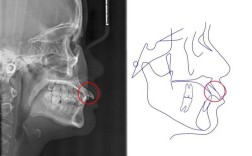

- 影像学检查(可能需要): 根据情况,医生可能会建议拍摄关节的X光片(如许勒位片)、锥形束CT(CBCT)或进行磁共振成像(MRI),以更清晰地观察关节盘、骨结构以及软组织的情况,排除器质性病变。